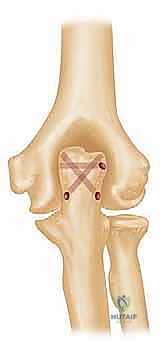

3. إزالة العظام المحطمة وتحضير القناة العظمية

بمجرد الوصول إلى المفصل، يتم تقييم حجم الدمار. تُزال الشظايا العظمية المفتتة التي لا يمكن إنقاذها. بعد ذلك، يتم تحضير القناة الداخلية لعظم العضد (من الأعلى) وعظم الزند (من الأسفل) باستخدام أدوات قياس دقيقة جداً لضمان تطابق المفصل الصناعي مع تشريح المريض.

يتم استخدام المفصل الصناعي النهائي، والذي يتكون غالباً من سبيكة معدنية عالية الجودة (مثل الكوبالت والكروم أو التيتانيوم) مع بطانة من البولي إيثيلين لضمان حركة سلسة. يتم تثبيت جذوع المفصل داخل العظام باستخدام "الإسمنت العظمي الطبي" (Bone Cement) الذي يضمن ثباتاً فورياً وقوياً، وهو أمر حاسم لمرضى هشاشة العظام.

6. ربط المفصل وإغلاق الجرح

بعد جفاف الإسمنت، يتم ربط جزئي المفصل (العضد والزند) معاً بمحور معدني (Linked Prosthesis)، مما يمنع خلع المفصل مستقبلاً. يعيد الدكتور هطيف بناء الأوتار (خاصة وتر العضلة الثلاثية) بدقة متناهية، ثم يتم إغلاق الجرح تجميلياً.